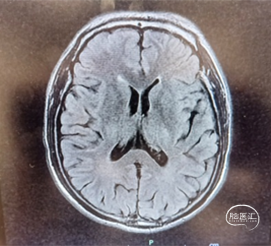

T1

T2 Flair

重要影像结论:头MRI示:1、脑干、左侧小脑、双侧额顶叶、双侧颞叶、双侧岛叶、胼胝体、右侧丘脑、双侧基底节区、双侧放射冠区、双侧半卵圆中心、双侧侧脑室周围多发腔隙性脑梗死、缺血灶,部分软化灶伴胶质增生。2、脑白质病变、双侧大、小脑萎缩。